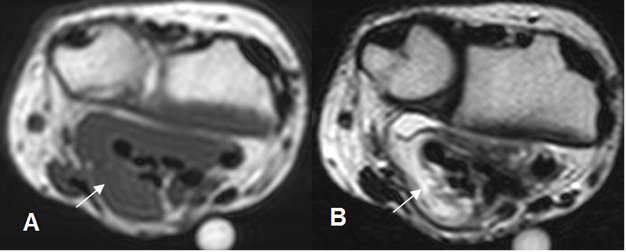

Fig 112 B. Fibromatosis.

A: RM axial en T1 y B: RM axial en T2. Presencia de tejido inflamatorio agudo hipointenso en T1 e hiperintenso en T2, que rodea los tendones flexores, a nivel de la muñeca.